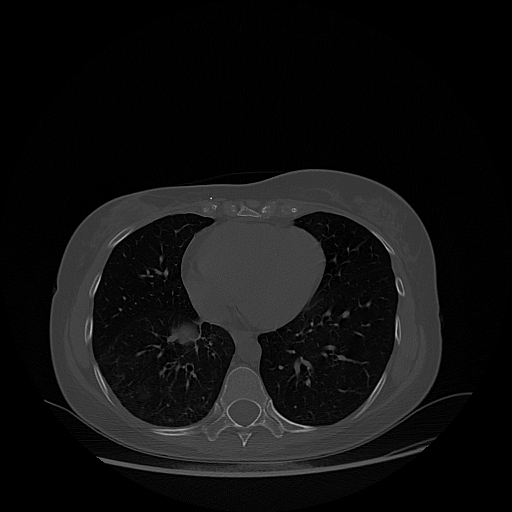

Image Grid

4Γ—3 grid: Rows show different image types (Original NATIVE, Reconstructed NATIVE, Original VENOUS, Generated VENOUS), Columns show windowing techniques (No Window, Lung Window, Mediastinum Window)

Reconstructed NATIVE CT scan (cycle consistency)

Full window (WL 1023.5, WW 4095 β†’ Low βˆ’1024, High +3071)

Lung window (WL -600, WW 1500 β†’ Low βˆ’1350, High +150)

Mediastinum window (WL 40, WW 400 β†’ Low βˆ’160, High +240)